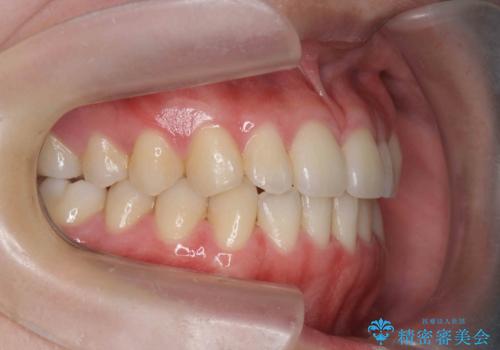

マウスピース矯正で前歯のガタつきを改善

- 上下の前歯のガタつきの改善を求めて、矯正治療を希望され来院されました。

矯正検査の結果、マウスピース矯正システム インビザラインの適応であることからワイヤーを用いず矯正治療を進めることとしました。

1日20時間以上の使用時間をきっちりと守っていただけたため、良好な治療結果、歯並びを手に入れることができました。